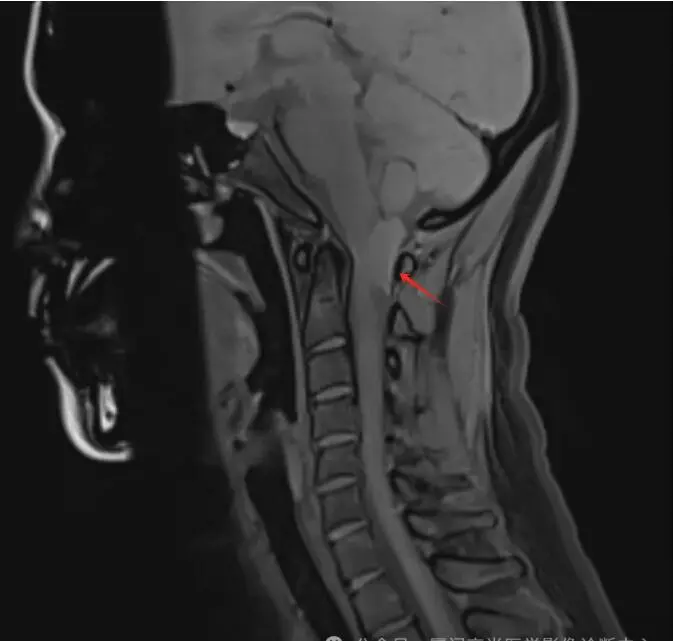

林女士,40岁,左侧头颈部疼痛1年,一直以为只是偏头痛,药物治疗,但效果甚微。后来到我中心做了头颅磁共振平扫;颈椎磁共振平扫+增强,终于发现症结所在。

磁共振图像

T2平扫

检查所见:检查发现其C1椎体-向上枕大孔上部水平椎管髓外硬膜下占位,考虑是脊膜瘤。